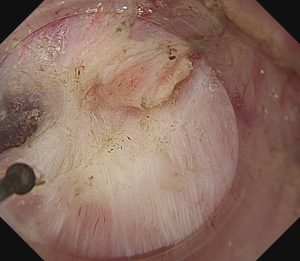

早期胃癌(SM浸潤がん)ESD